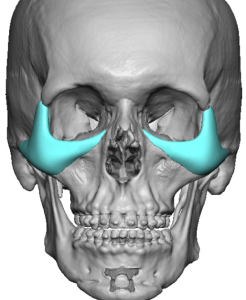

Advantages of Custom Implants

Standard implants frequently fall short because NOV is a complex, three-dimensional, patient-specific problem.

Custom (patient-specific) implants:

- Are designed from CT scan data

- Precisely match orbital rim curvature and asymmetry

- Can extend into multiple regions, including:

- Infraorbital rim

- Pyriform aperture

- Maxilla

- Allow controlled forward projection where needed

Eppley-Style Custom Implants for NOV

The core principle is not simply augmenting the infraorbital rim, but reconstructing the entire midface support platform in a continuous, anatomically blended way.

Core Design Philosophy

- Treat NOV as a global skeletal deficiency rather than a localized defect

- Create a smooth, continuous augmentation from:

- Medial infraorbital rim ? central rim ? lateral rim

- Extend inferiorly and laterally onto the cheek

- Avoid step-offs or isolated projection that appears unnatural

Implant Design Components (Single Integrated Piece)

1. Infraorbital Rim Augmentation

- Saddles the infraorbital rim

- Adds both vertical height and horizontal projection

- Produces a superoanterior (3D) expansion of the rim

- Enhances lower eyelid support